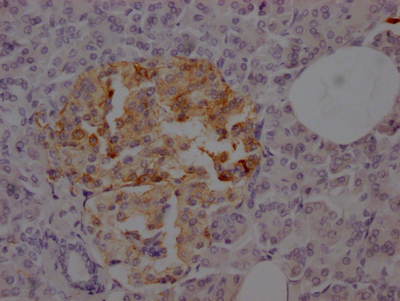

ApplicationELISA, IHC; Recommended dilution: IHC:1:50-1:200